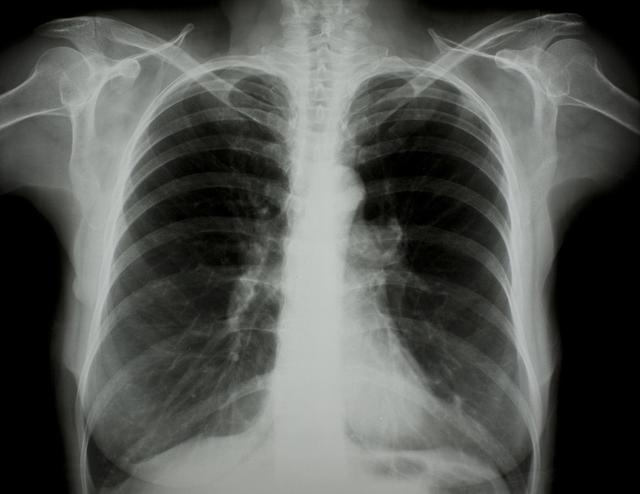

涪陵地區(qū)最新肺炎情況顯示,疫情形勢嚴峻。目前,當?shù)卣歪t(yī)療部門正在積極應(yīng)對,采取一系列措施控制疫情傳播。具體感染人數(shù)、癥狀表現(xiàn)、疫苗接種情況等仍在持續(xù)更新中。請廣大市民密切關(guān)注官方發(fā)布的信息,做好個人防護,共同抗擊疫情。涪陵地區(qū)肺炎疫情嚴峻,政府積極應(yīng)對,請市民關(guān)注官方信息,加強個人防護。